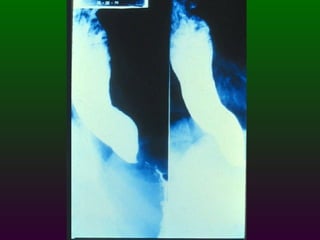

SEGD PATOLOGÍA  ESOFÁGICA A.- Estrechamientos y dilataciones secundarias Acalasia Estenosis Esclerodermia Enf. de Chagas Neoplasia Lesiones por quemadura (cáusticos y dietéticos etc.)